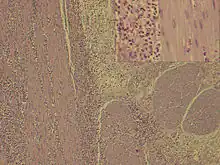

| H&E stain: Dense eosinophilic infiltration of gastro-duodenal wall | |

Definitive diagnosis involves histological evidence of eosinophilic infiltration in biopsy slides. Microscopy reveals >20 eosinophils per high power field.[12][20] Infiltration is often patchy, can be missed and laparoscopic full thickness biopsy may be required.